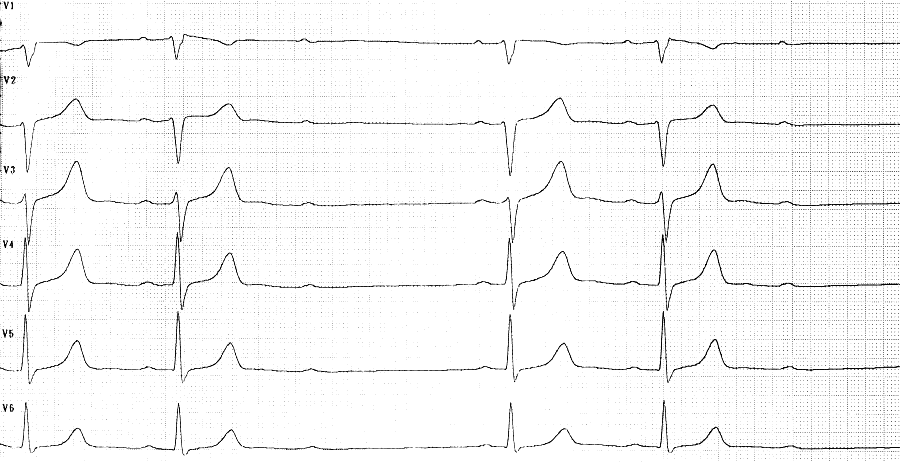

- Indifferenztyp

- Sinusrhythmus

- HF 70/min

- Zeiten: P 0,10s

PQ 0,16-0,20s QRS 0,09s QT 0,36s (QTc

0,39s)

Formveränderungen + Rhythmus:

- zunehmende PQ-Verlängerung

- Blockierung der AV-Überleitung

bei jeder dritten P-Welle

- QRS-Morphologie bis auf angedeutete

rSr'-Konfiguration in V1 unauffällig

Diagnose

1. AV-Block II. Grades Typ Wenckebach

(3:2-Überleitung)

2. V.a. inkompletten RSB